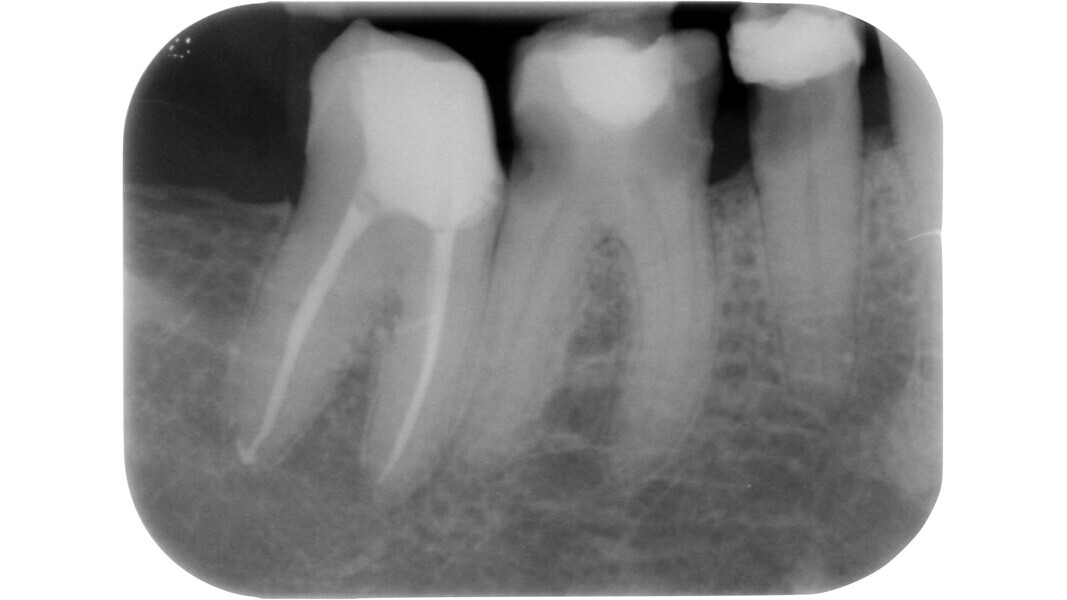

Fig. 13 : Emplacement des mesures effectuées par Deutsch et al.8, 9 sur une molaire inférieure analysée par micro-TDM (avec l’aimable autorisation du Prof. Elio Berutti).

Dans les molaires, la distance entre la pointe d’une cuspide et le plafond de la cavité pulpaire est d’environ 6,3 mm, tandis que dans les prémolaires supérieures, elle est de 6,94 mm. La cavité pulpaire a une hauteur d’environ 1,5 à 2 mm et la distance moyenne entre le plancher de la cavité et la furcation est d’environ 3 mm (Tableau 1) (Fig. 13).